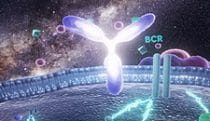

Look & feel for targeted mAb MOA

Look & feel explorations -

Monoclonal antibodies

Work -

Antibody binding

Work -

antibody and villi

Work -